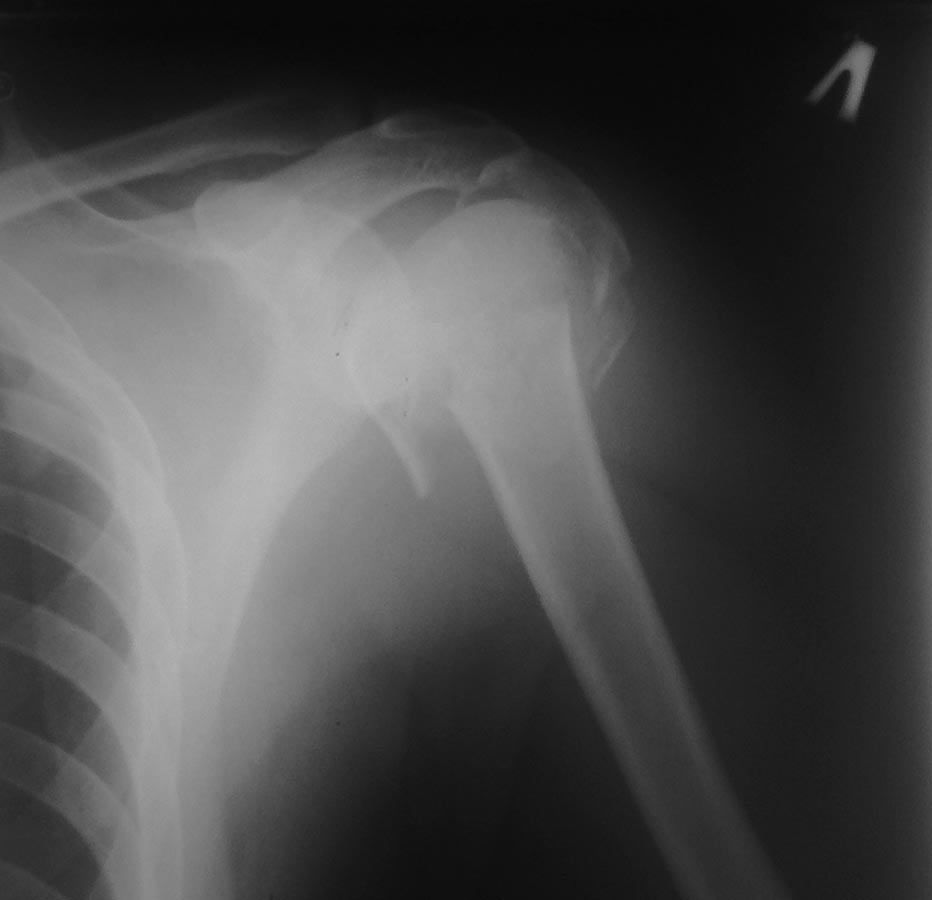

Проксимальный перелом плеча надо выяснить, состоит из скольких частей? Если из трех, тогда фиксировать пластиной, или если из 4х фрагментов тогда остеонекроз головки обеспечен, можно оставить в косынке. Со временем будет видно, иногда на остатке костного остова получается неплохой результат...

Наша тактика, независимо от времени поступления, ургентная фиксация шейки бедра, через пару дней фиксация бедра дистальной пластиной и надколенника. Затем фиксация плеча.

Здесь выставлен ренгенограммы больного, ему 21, травму получил в результате высокоскоростной погони на украденной машине, которая закончилась смертью трех остальных “боевых комрадов”. Начатую коллегой открытую операцию на шейке пришлось закончить мне, установкой винтов и ретроградной фиксацией бедра. Выписка в обычное сроки и наблюдался амбулаторно. Каждый раз напоминали о возможности осложнений ввиде несращения! По истечению 4 месяцев появились признаки варусной деформации. На СТ срезах несращение шейки и бедра. Риминг, замена на более толстый гвоздь и вальгусная остеотомия.